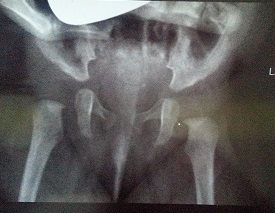

wtórna panewka PDF Drukuj Email

Jak rozpoznać tworzenie wtórnej panewki :

Pewne cechy mogą nam zasygnalizować wytworzenie wtórnej panewki na przykład:

-płytka panewka proporcjonalnie do głowy lub drugiego stawu;

-głowa oddalona od panewki w gorszym typie;

-jeśli w trakcie badania widzimy dwa różne typy stawu (w tym zwichnięty co najmniej D) ,który da się poprawić to należy rozważyć powstanie wtórnej panewki ;

-asymetria w odwiedzeniu stawów która jest zauważana podczas przeprowadzania badania klinicznego i której nie da się skorygować;

-różny wygląd obu stawów ; asymetria w wypukłości pachwiny spowodowana przesunięciem głowy kości .

w razie jakichkichkolwiek watpliwosci od 3 miesiaca zycia ;badanie RTG jest konieczne.